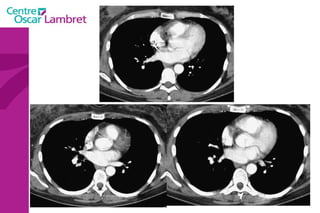

Le médiastin C'est l’espace au centre du thorax. Il est situé en avant de la colonne vertébrale et peut être divisé en plusieurs quadrants.  Il est divisé, par convention, en : médiastin postérieur :  contenant notamment  l’oesophage et l’aorte descendante.  médiastin moyen :  contenant les voies aériennes supérieures : trachée et sa division (carène).  médiastin antérieur :  contenant le cœur, l’aorte ascendante, les artères pulmonaires et la veine cave supérieure.

Le médiastin Le médiastin   antérieur  comprend : L’aorte ascendante Le tronc pulmonaire La veine cave supérieure Les cavités cardiaques sauf l’atrium gauche La loge thymique

Le médiastin Le  médiastin moyen  comprend : La trachée La carène Les pédicules pulmonaires : Les bronches souches Les veines et les artères pulmonaires Le segment horizontal de la crosse de l’aorte Le Tronc Artériel Brachio-Céphalique L’artère carotide primitive gauche La crosse de la grande veine azygos

Le médiastin Le médiastin  postérieur  comprend : Le canal thoracique La grande veine azygos et les veines hémi azygos L’œsophage L’aorte descendante et ses branches

Le médiastin